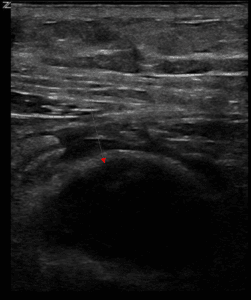

A 59-year-old gentleman with end stage renal disease, coronary artery disease, type 2 diabetes, and hypertension was admitted to the hospital for dyspnea due to mild volume overload. On physical exam, he was noted to have a 3 x 3 cm soft tissue mass on the right forehead with superficial ulceration (Figure 1). His medication list did not contain any anti-platelet agents or anticoagulation. The patient described a hematoma since a mechanical fall while walking on the street 6 weeks prior with impact to his forehead. He had developed swelling immediately after the fall but did not lose consciousness. He presented to the emergency department (ED) at that time where CT head was performed showing a 3 cm prominent right prefrontal soft tissue hematoma. A needle aspiration was performed with reportedly over half of the fluid in the hematoma drained. He was discharged from the ED. Given increased swelling and pain at the site of the hematoma, he returned to the ED 1 week later where the soft tissue swelling was noted to be 4 cm. Given persistent pain, a repeat needle aspiration was performed and 7 ml of blood was removed. Incision and drainage was also performed with clotted blood removed and he was discharged. Fluid specimens were not sent for laboratory analysis at either visit.

Figure 1. Images of right forehead soft tissue mass.